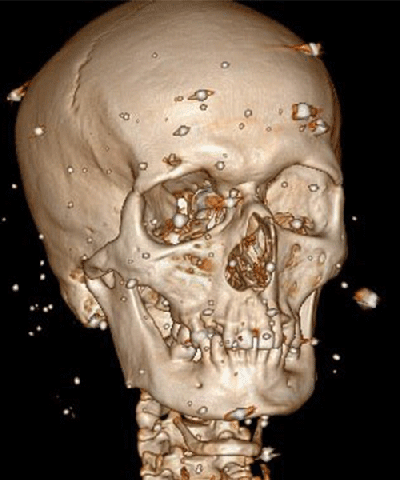

The injuries were of various types, including open craniocerebral trauma, amputated extremities, injured faces and thoracic-abdominal wounds with internal bleeding. The peculiarity of the soldiers was that they received bullet penetrating wounds through parts of the body not covered by body armor and helmet, for example, through the upper aperture of the chest, hot metal fragments up to 15-20 mm penetrated into the mediastinum and stuck to the wall of the main vessels or myocardium, which could only be removed in a specialized center.

Until the process of evacuation, both from them and to them, was settled, the wounded, the so-called 300, were being transported constantly day and night. These were critical injuries to the whole body, polytrauma, multiple foreign bodies in the neck near the vessels, and closed head injuries, hemopneumothorax, fractures of the ribs, shoulder blades, multiple fragmentation fractures of the pelvis, and avulsion fractures of the limbs, with long defects that often required amputation. Massive deformed soft tissue defects with multiple metal fragments from cluster munitions. Penetrating gunshot blind wounds of the abdominal cavity, liver and spleen ruptures with complicated internal bleeding, ureteral ruptures, post-traumatic aneurysms, damage to the pelvic organs and much more. Our military surgeons, anesthesiologists and everyone involved tried to save everyone at all stages of the evacuation, almost all of them already had experience in combat conditions since 2014.